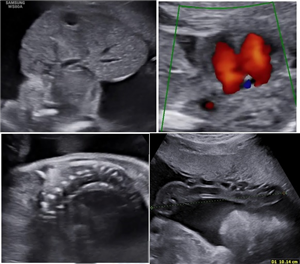

CLS: Siêu âm tim thai thông liên thất